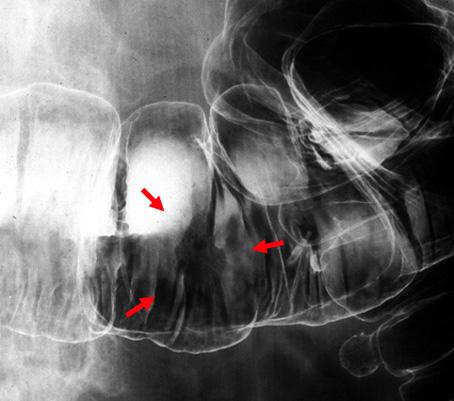

Type 0-IIc (superficial depressed type) early colon cancer showing marginal irregularity and unevenness of the shallow depression.

Malignant epithelial tumor/Adenocarcinoma

Large intestine(Colon)/Transverse colon

X-ray

Type 0/IIc (IIc) Superficial depressed type

15 - 19

mucosa